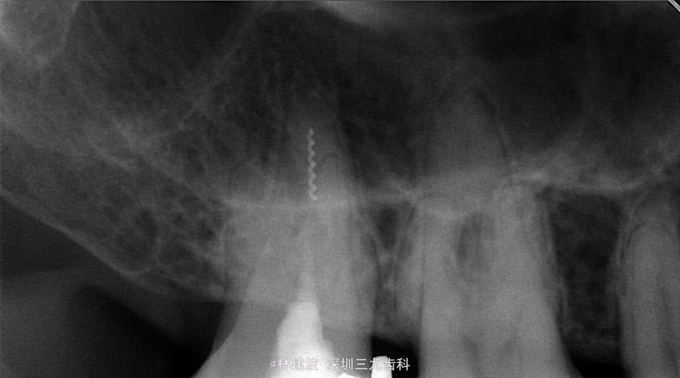

17残冠,X片示:腭根内见折断根管输送针。

显微镜下超声器械取出陈旧性折断器械,再次根管预备封药。